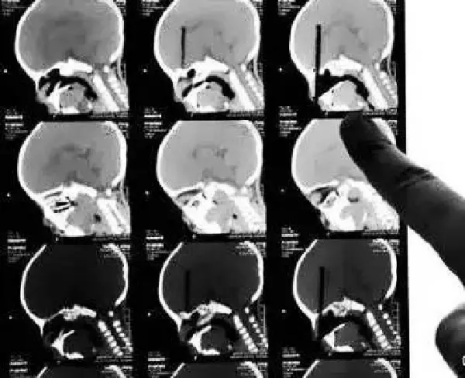

CT

CT的檢查原理是X光會(huì)斷層穿過人體,通過電腦計(jì)算后處理為二次成像。

優(yōu)點(diǎn):可以斷層看,經(jīng)后處理可以顯示更多信息。

缺點(diǎn):費(fèi)用比X光攝影貴,且CT檢查的輻射劑量通常高于單次X光攝影。

(筷子插入小朋友眼球的CT三維重建片)